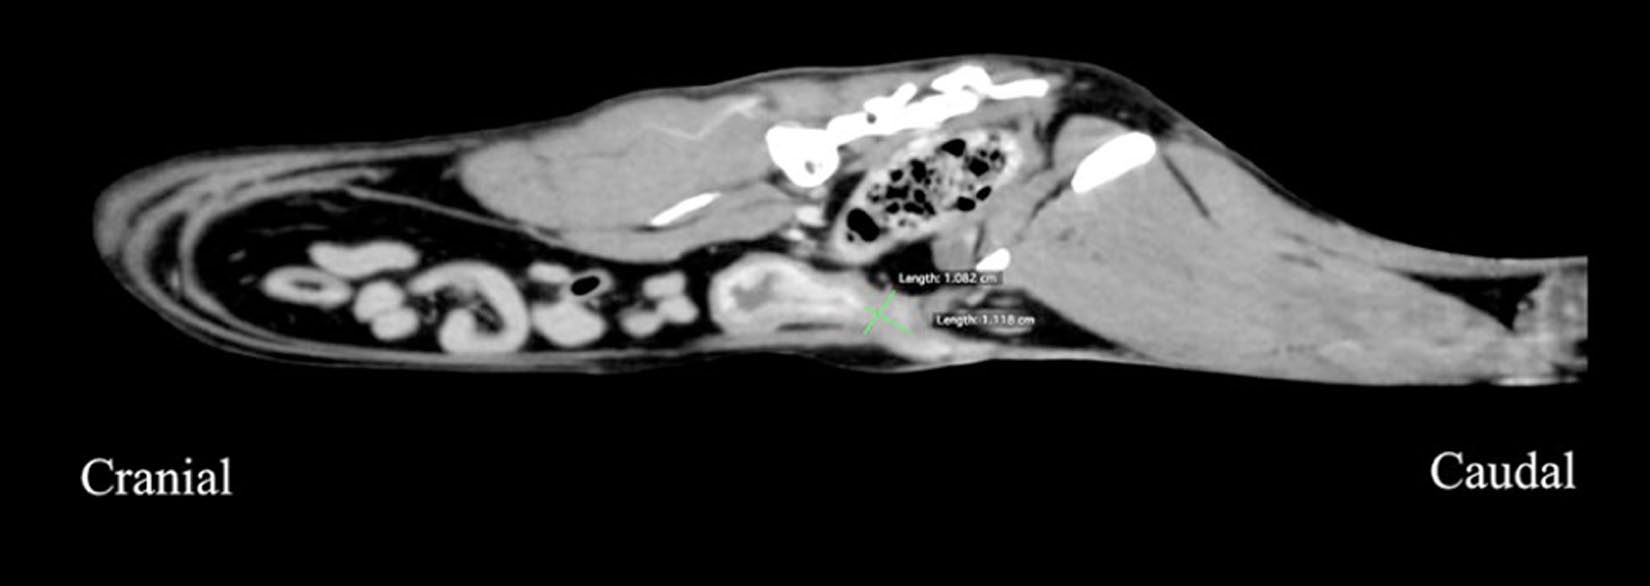

CT未见泌尿系结石或解剖异常,但腹膜内尿道因既往尿道吻合术及重建术变短(约11 mm)且不规则(图1)。随后行无菌手术。术中及术后持续输注多巴胺2.5–5.0 µg/kg/min和芬太尼1.25–10 µg/kg/h,并静脉给予氨苄西林20 mg/kg。

图1. 术前腹部增强CT矢状位图像:因曾接受耻骨前尿道造口及尿道重建等手术,腹膜内尿道被缩短至约11 mm,形态不规则,解剖结构显著改变。矢状位CT示术后腹腔内尿道缩短至11 mm且形状不规则。

本例通过增强CT精确测量腹内段尿道仅长11 mm,为选择袖套尺寸提供关键依据。超声与平片受肠道气体及术后解剖变异影响,难以量化尿道长度与内径,提示复杂泌尿道畸形应首选CT排泄期造影。